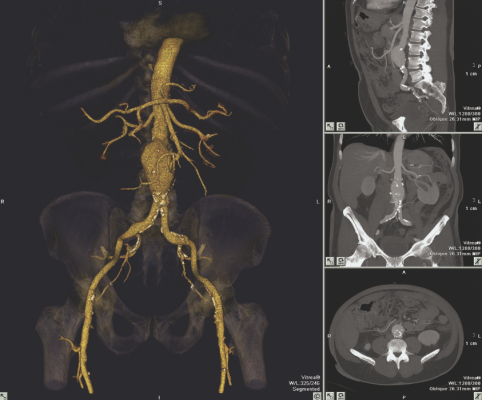

Vital's denoising filter, Structure Preserving Diffusion (SPD), focuses on increasing image quality by improving the appearance of noisy images for computed tomography (CT) and X-ray angiography. It addresses the noise challenges presented by today's CT protocols. SPD can be used with any scanner generation in conjunction with iterative reconstruction (IR) techniques to enhance diagnostic interpretation. Denoising filters are applied in all available viewports; e.g., MPR (multiplanar reformat), CPR (curved planar reformat), 3-D and other volumetric views. Denoised series can then be stored with the original source images in picture archiving and communications systems (PACS). Built to work with existing hardware, users have the ability to create and save their own denoising filters.

"Image Denoising helps customers see a clear view of anatomy from noisy scans without changing the integrity of the image," said Jim Litterer, general manager at Vital. "In terms of efficiency and productivity, denoising is a game-changer. Technologists no longer have to spend hours sorting through the noise to get clear images."